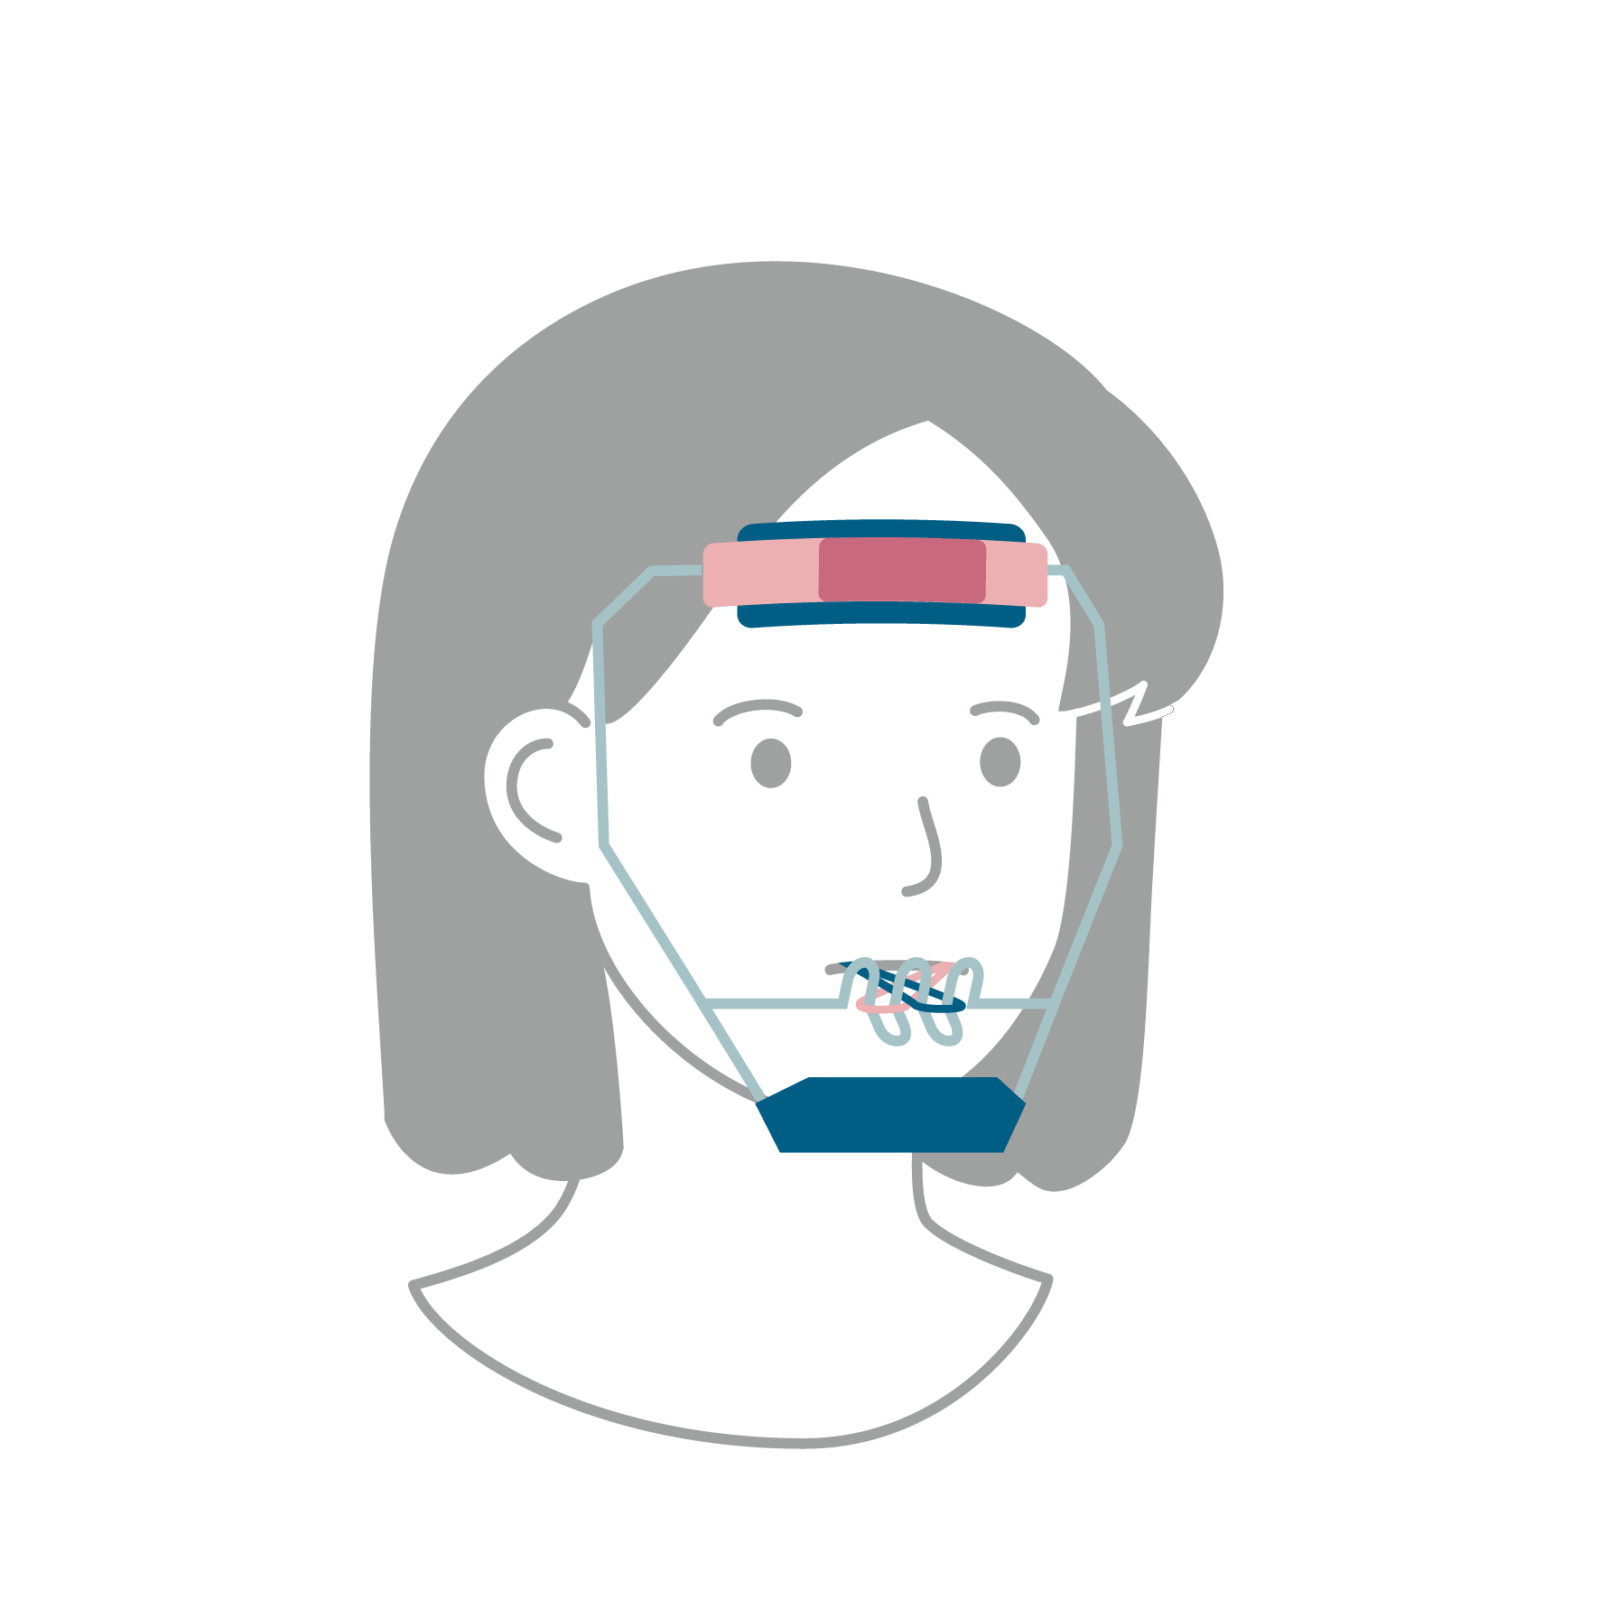

治療開始時期の目安は、6~8歳前後の早めの時期が望ましいといえます。受け口の場合、骨格的な問題があることが多く上あごの成長が足りず下あごが前に出てしまっている状態のため、思春期でのさらなる下あごの成長に備えて、上顎前方牽引装置(じょうがくぜんぽうけんいんそうち)などの装置を使用して上あごを成長させておく必要があります。

ワンポイント

はやめに相談して「経過観察だけでOK」なのか、「今から装置を使った方がいいのか」を見極めることが大切です。